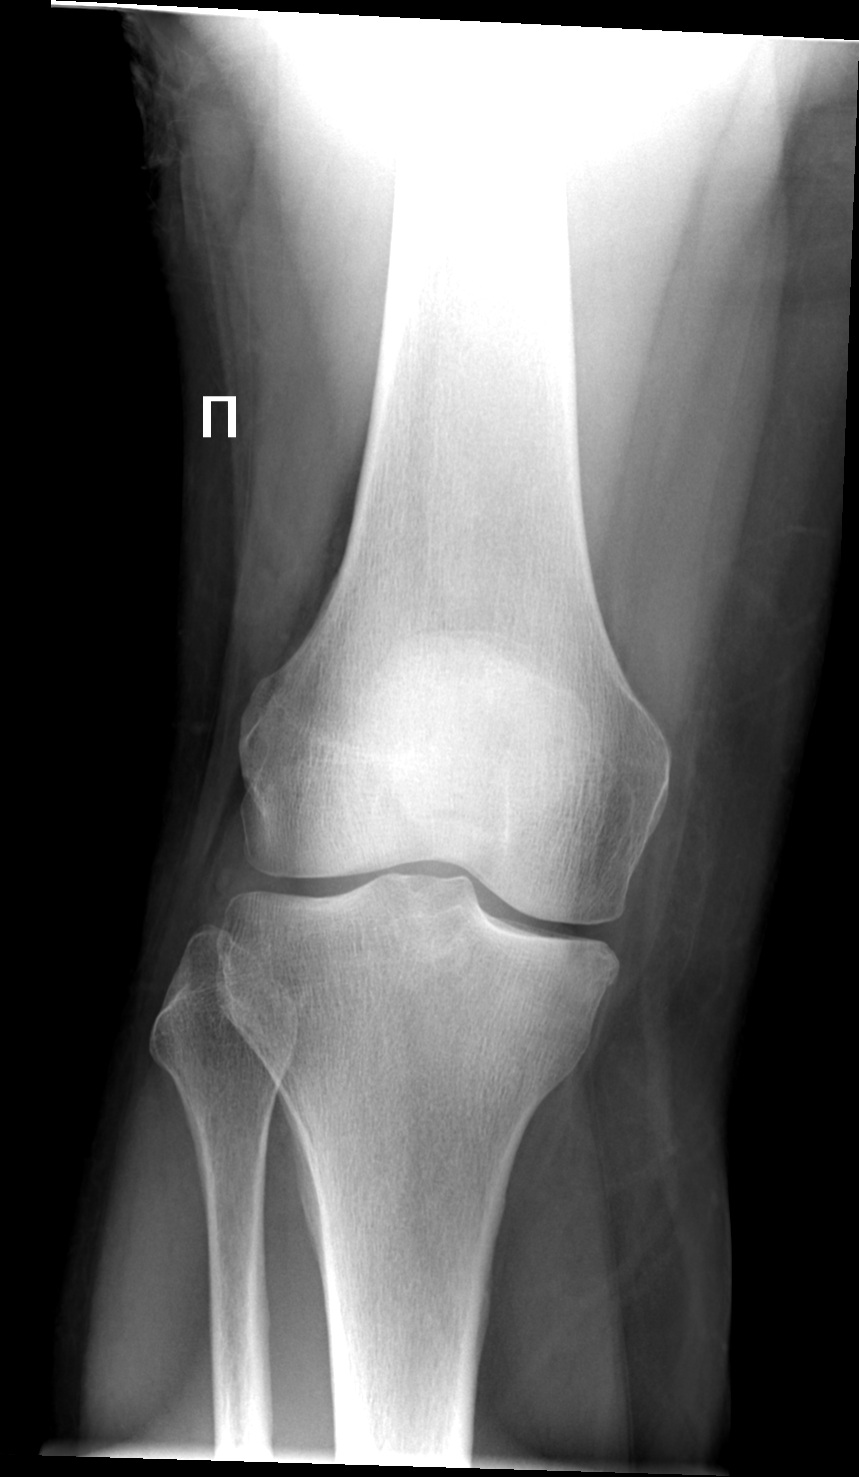

Пациентка 1961 от терапевта с жалобами на боли в правом колене с направительным диагнозом гонартроз? Ассиметрия мыщелков бедренных костей, мыщелки большеберцовой кости на разных уровнях. Дисплазия?

Не определю ширину щелей. А так ДОА 1 ст.

Правосторонний гонартроз 0-1 ст.

Да не, вроде нет дисплазии, косо укладено))

На мой взгляд, центр луча попал выше нижнего полюса надколенника. От этого суставная щель выглядит более суженной, чем на самом деле.